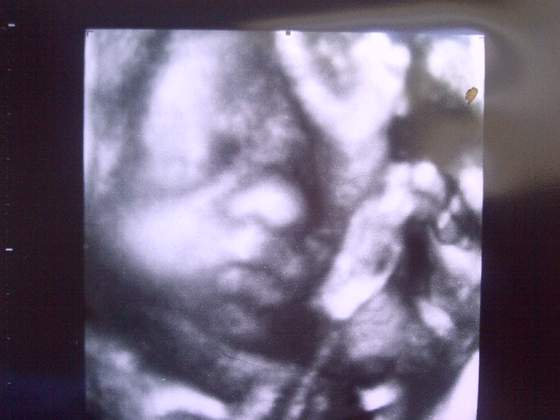

Grudnioweczka jaka mala spiaca krolewna